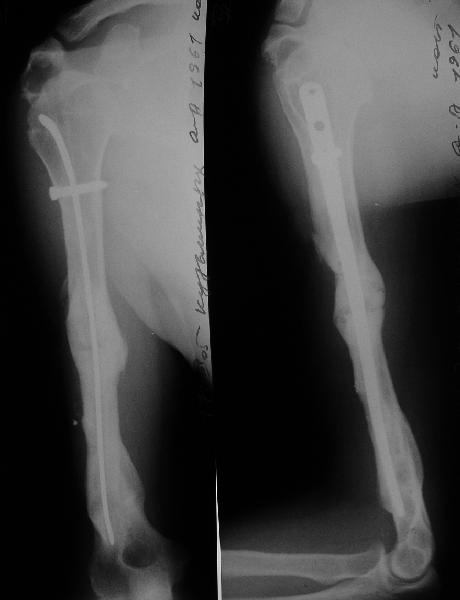

Такие надмыщелковые переломы в изолированном виде у нас в последние годы обычно фиксируются плоским титановым стержнем a la Зверев-Ключевский антеградно. Но тут еще и вышележащие проблемы.

Наверно, можно пойти на укорочение, убрав металлический цилиндр, не такой уж большой дефект. Снимки в чем-то похожего пациента прилагаю - тоже несращение диафиза после многократных операций, и надмыщелковый свежий перелом (случился после удаления обломка стержня аппарата).